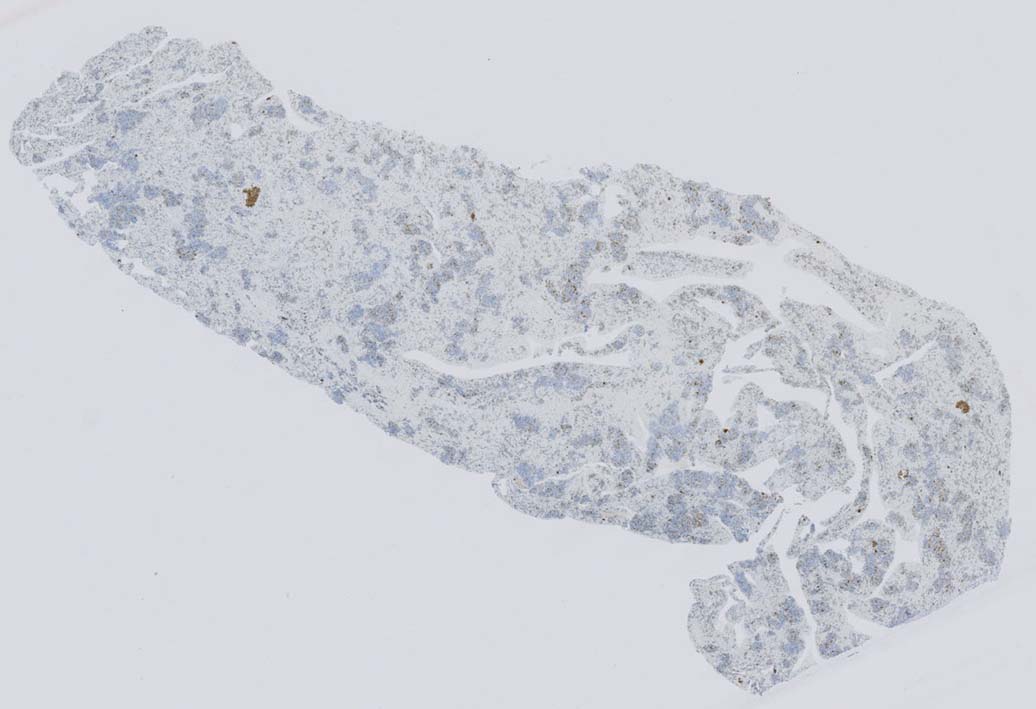

同じ患者さんの骨髄所見です. (サムネイルのクリックで大きな画像が見られます.)

骨髄への腫瘍細胞浸潤はintertrabecular patternで, 腫瘍細胞は小集簇巣を形成して散在性に認められた. HE, ASD-Giemsaのみでの浸潤, 増殖の確定はなかなか難しいようです.

ASD-GiemsaではASDに染まらない(陰性の)あやしい細胞塊があるように見える. 細胞小塊はCD3陽性.

骨髄クロットでは, 十分量が採取されているにもかかわらず, CD3陽性細胞は微小な集簇巣が2個ほど認められるのみであとは散在している.

免疫染色でCD3陽性となる細胞集塊のASD-Giemsa像. 肝類洞内浸潤細胞に比較して核, 細胞が紡錘形の傾向を示している.